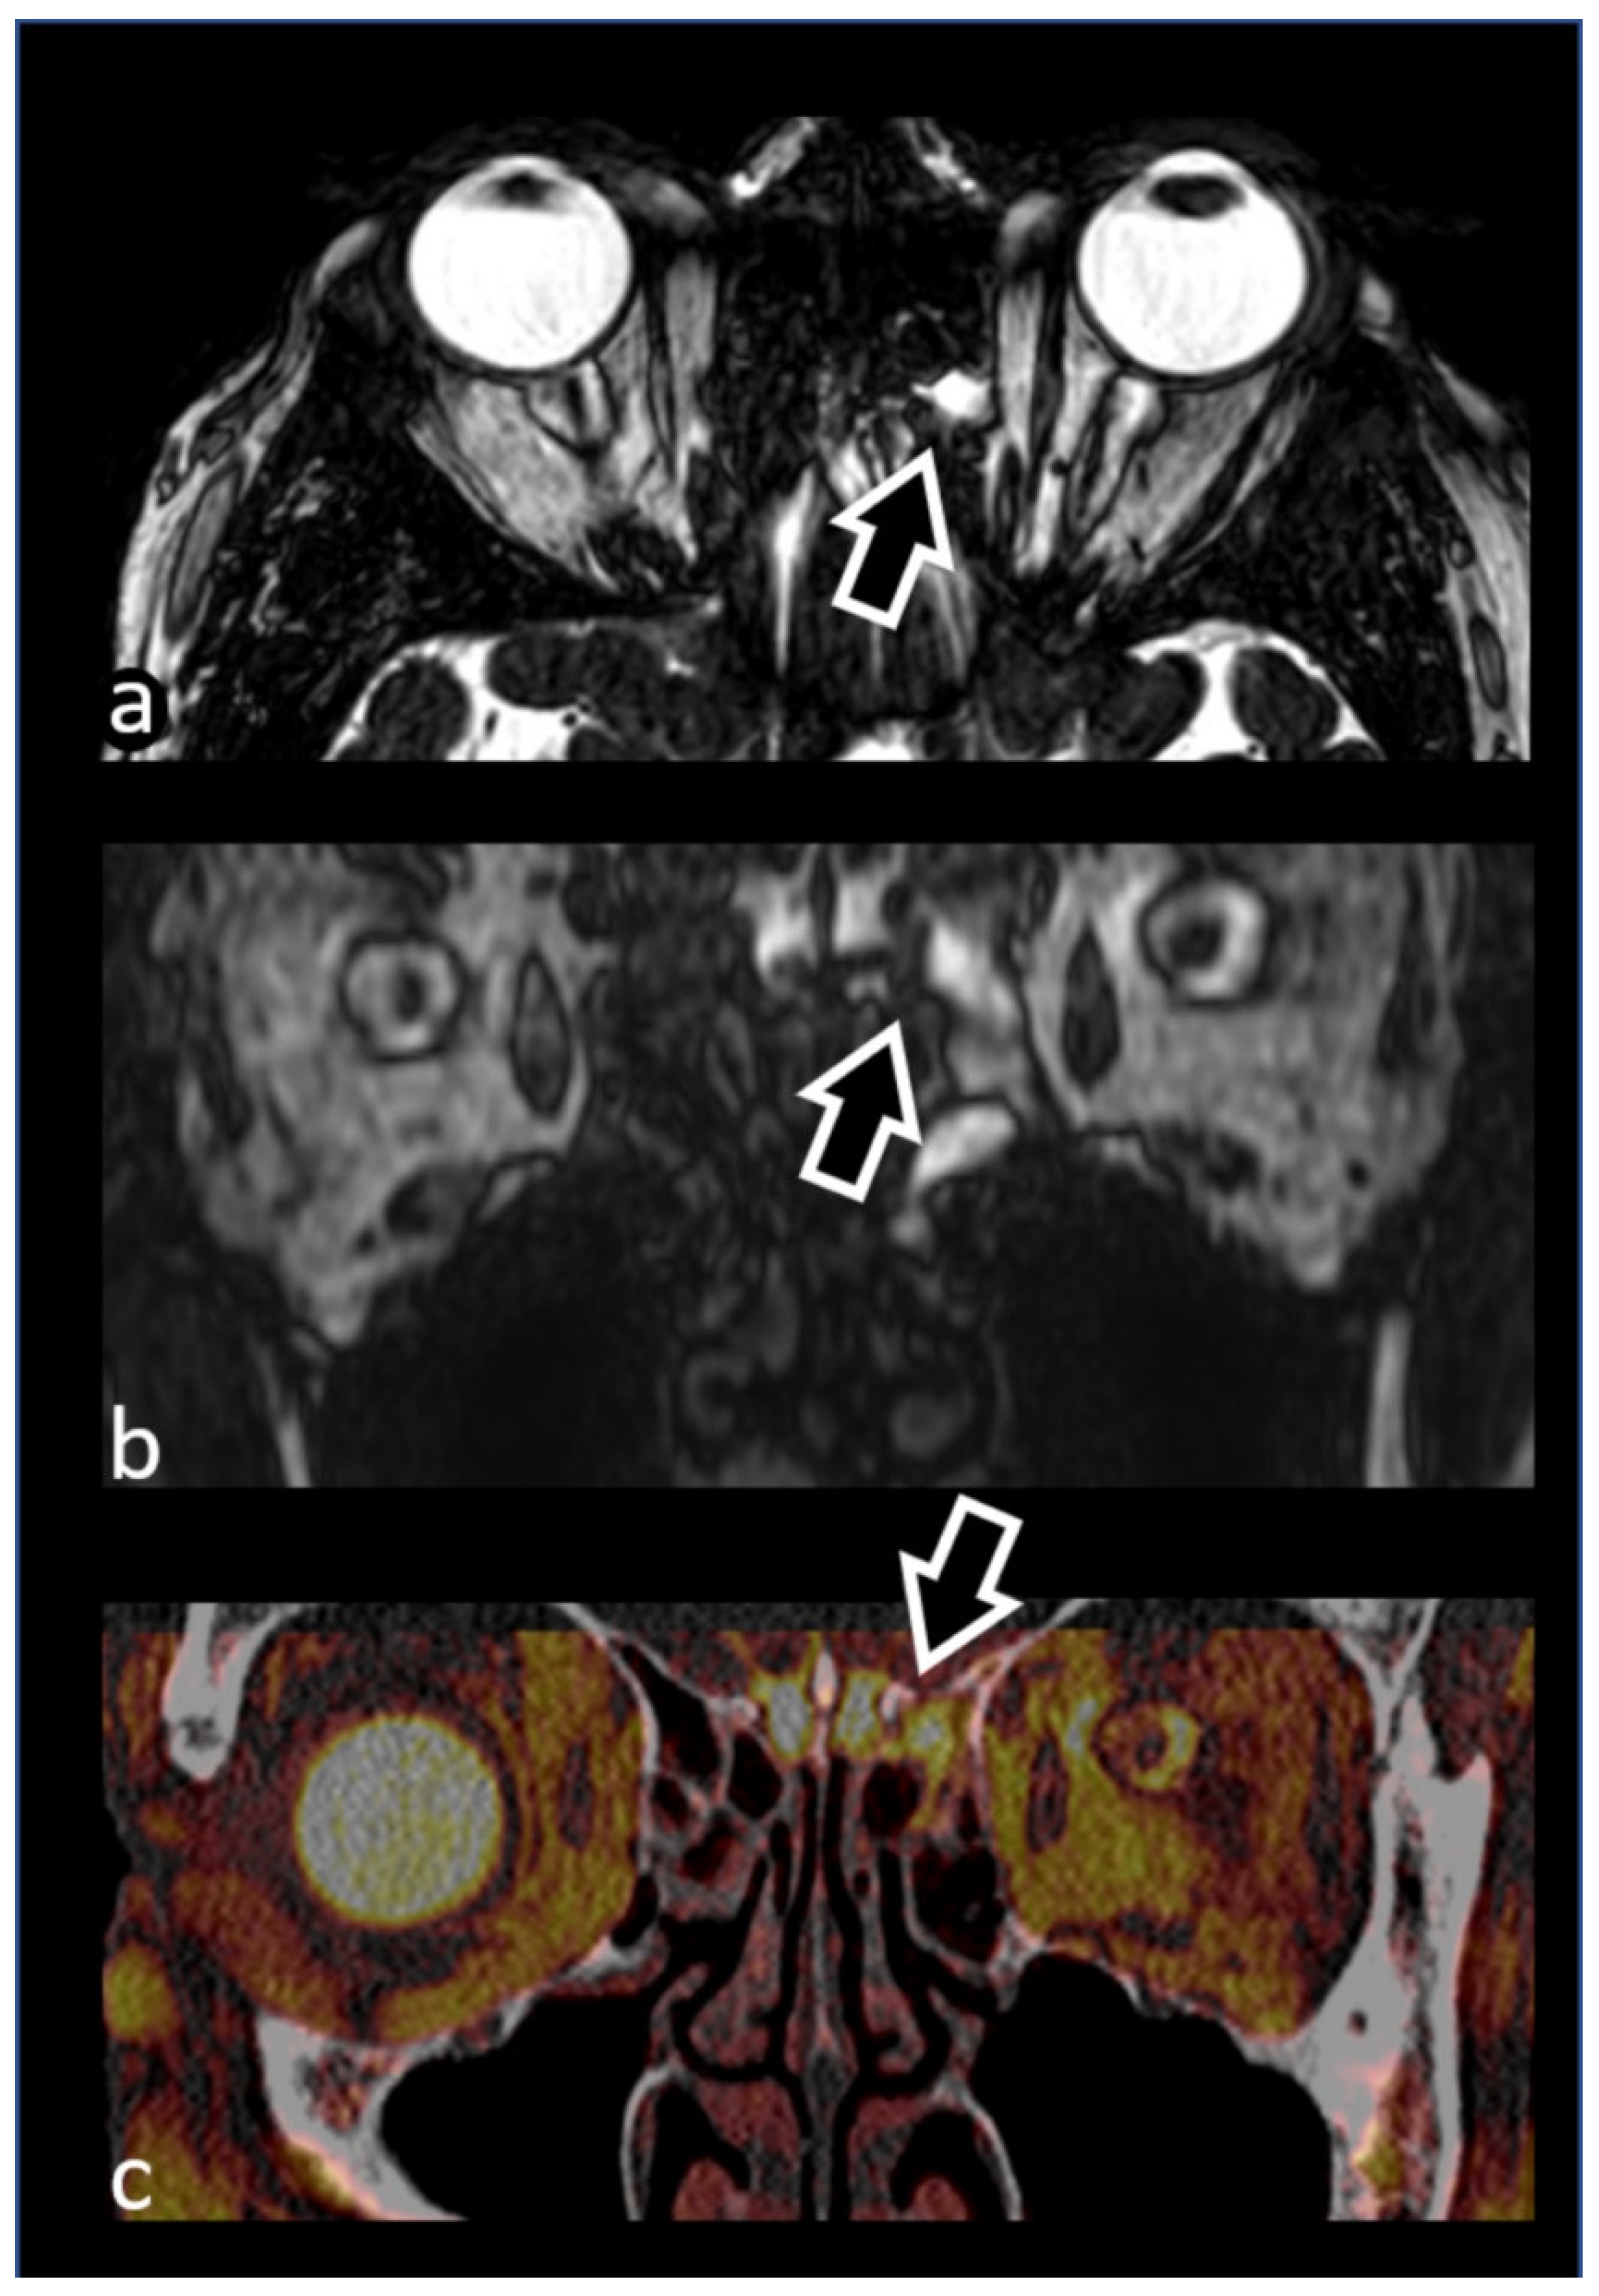

3.1. Evaluation of Cranial Nerves

3.1.4. Trigeminal Nerve (V)